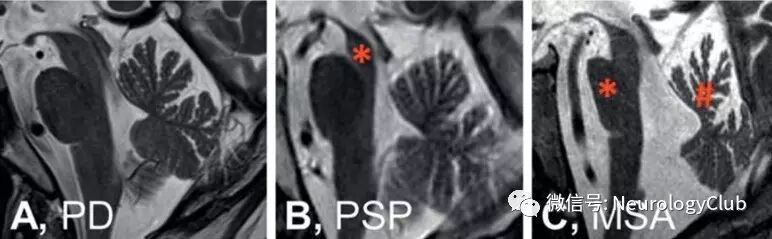

图2:在磁共振扫描中,脑干的正中矢状位提示帕金森氏病(PD)患者无明显特异性萎缩(图A),进行性核上性麻痹(PSP)患者可见中脑萎缩(*)(图B),多系统萎缩(MSA)患者可见脑桥萎缩(*)和小脑上蚓部萎缩(#)

图3:还有一些磁共振征象可以提示MSA,但并非高度敏感性的。T2WI序列脑桥可出现十字形高信号(脑桥十字征,*,图D),壳核可见低信号(*)伴边缘边缘高信号(壳核裂隙征,,图E